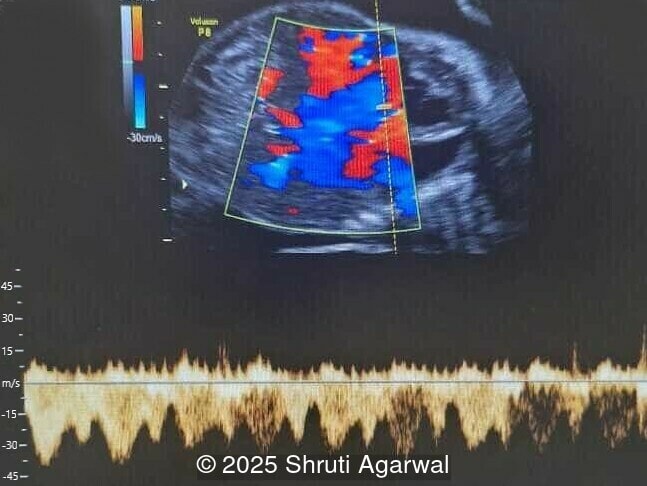

- Image 5: normal cardiac inflow

Chorangiomas greater than 5cm are referred to as a giant chorangioma and occur in approximately 1 in 2,700 pregnancies [2]. Giant chorangioma can be clinically significant, causing various fetomaternal complications. In a study reviewing 175 cases of chorangioma, approximately 34% of giant chorangiomas experienced complications [2]. Arteriovenous shunting in giant chorangioma can increase venous return to the fetal heart, causing hypervolemia, tachycardia, and cardiomegaly, leading to heart failure, hydrops fetalis, and fetal demise. Large lesions can also divert nutrients and oxygen from the fetus, manifesting as growth restriction. Placentomegaly occurs due to a hyperdynamic circulation as a result of arteriovenous shunting. In such cases, fetus may suffer from anemia and thrombocytopenia due to sequestration of red blood cells and platelets by the tumor. Polyhydramnios can occur due to both direct transudation into the amniotic fluid and to fetal polyuria secondary to the hyperdynamic circulation. Additionally, preterm delivery and maternal mirror syndrome with generalized fluid overload and preeclampsia can occur with giant chorangiomas [2,8].

Prenatal diagnosis depends on ultrasound, however, chorangioma can cause an increase in maternal serum alpha-fetoprotein [3]. Ultrasound examination reveals a hypo- or hyperechoic, well-circumscribed mass, which is usually located underneath the chorionic plate near the umbilical cord insertion, and often protrudes into the amniotic cavity. Color Doppler demonstrates large vascular channels around and within the tumor [6,9]. In cases of giant chorangiomas, echocardiography should be performed to assess cardiac function and measure fetal middle cerebral artery peak systolic velocity for diagnosis of fetal anemia. Regular ultrasounds with Doppler studies are used to monitor tumor size, fetal growth, amniotic fluid volume, and signs of fetal anemia or heart failure. The frequency of exams is based on tumor size and associated complications. With small tumors, assessment may occur every 3-4 weeks, whereas in large tumors, the ultrasound scan may be done every 1-2 weeks [3]. These regular assessments can diagnose conditions that require intervention, such as polyhydramnios, hydrops, or hemolytic anemia.